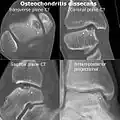

Computed tomography (CT) scans and Technetium-99m bone scans are also sometimes used to monitor the progress of treatment. Unlike plain radiographs (X-rays), CT scans and MRI scans can show the exact location and extent of the lesion.[39] Technetium bone scans can detect regional blood flow and the amount of osseous uptake. Both of these seem to be closely correlated to the potential for healing in the fragment.[40][41]

CT scan and projectional radiography of a case of osteochondritis dissecans of parts of the superior-medial talus.

Sagittal MRI: Linear low T1 signal at the articular surfaces of the lateral aspects of the medial condyle of the femur confirms the presence of OCD.